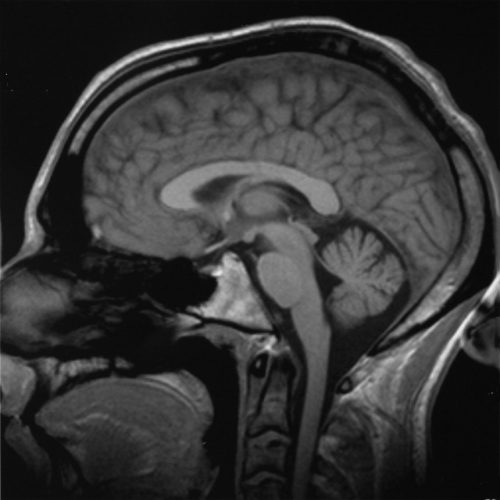

Neuroscience Scholars

This panel is for presenters participating in the Neuroscience Scholars Program. On August 30, Student Presentations begin at 2:00pm.